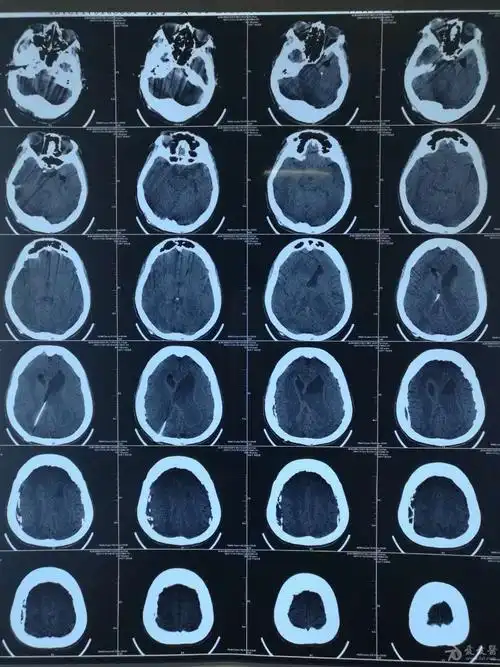

脑积水ct显示:侧脑室,三脑室扩大有症状的脑积水应该及时手术治疗.

脑积水ct影像

【读片】脑积水 [病例帖]

该脑积水病例手术指征明确明确吗

查头ct:后颅窝蛛网膜囊肿,重度脑积水(交通性),双侧小脑蚓部未见,考虑

交通性脑积水(正常颅压性脑积水)vp分流治疗一例

罕见脑积水病例